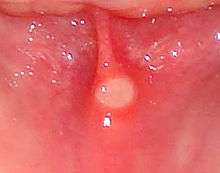

| A mouth ulcer (in this case associated with aphthous stomatitis) on the labial mucosa (lining of the lower lip). | |